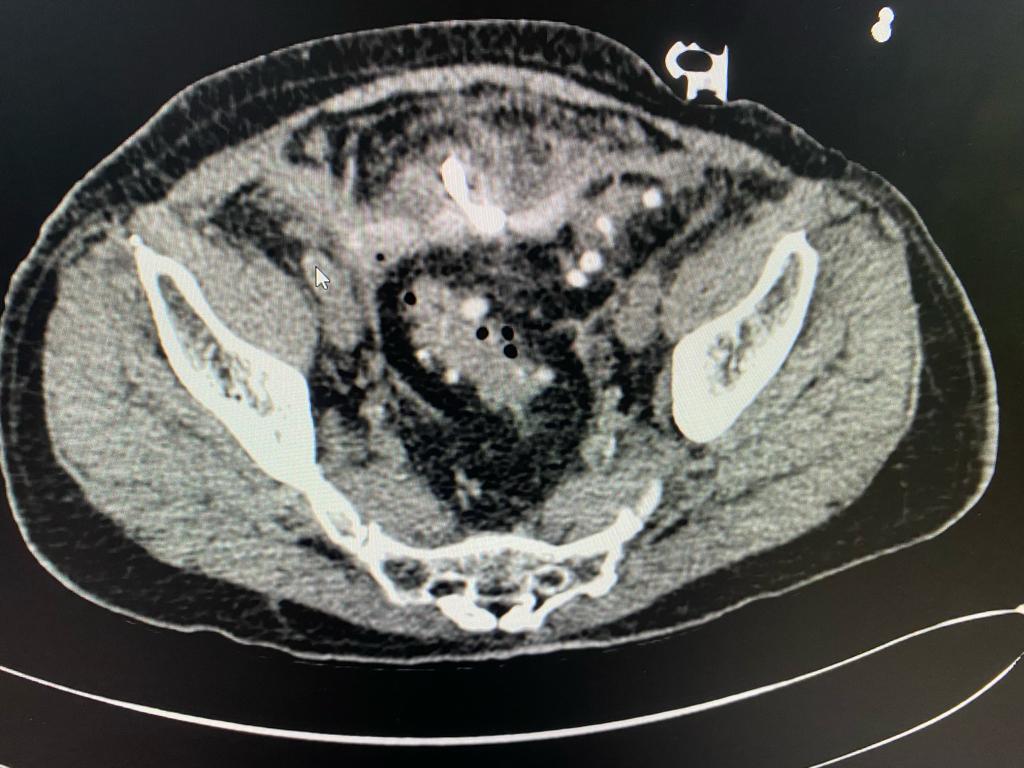

After admission, we reviewed the history, investigations, sequence of events and old CT scan. We suspected colonic diverticulosis with perforation as the original reason for sepsis. We repeated the CT scan of abdomen and pelvis which showed a pelvic abscess along with a sigmoid colonic diverticular phlegmon confirming diverticular perforation. The drain placed during previous laparoscopy was out of position. After a multidisciplinary meeting, treatment plan was charted out. The original drain was used to guide another drain deep in the pelvic abscess cavity under radiological guidance thus ensuring free drainage. The antibiotics were adjusted based on culture sensitivity of the intraabdominal pus. There were multiple highly resistant organisms and very few antibiotics were available for treatment. Hence the definitive surgery was deferred. Patient recovered and was sent home on intravenous antibiotics and drainage catheter.